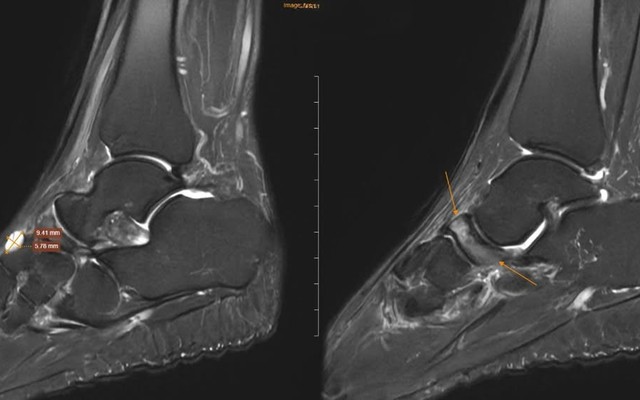

Sống khỏe 2026-03-27T17:00:00Đi khám vì đau cổ chân không rõ nguyên nhân, nữ giáo viên phát hiện ra xương bên trong đang bị tự hủy.